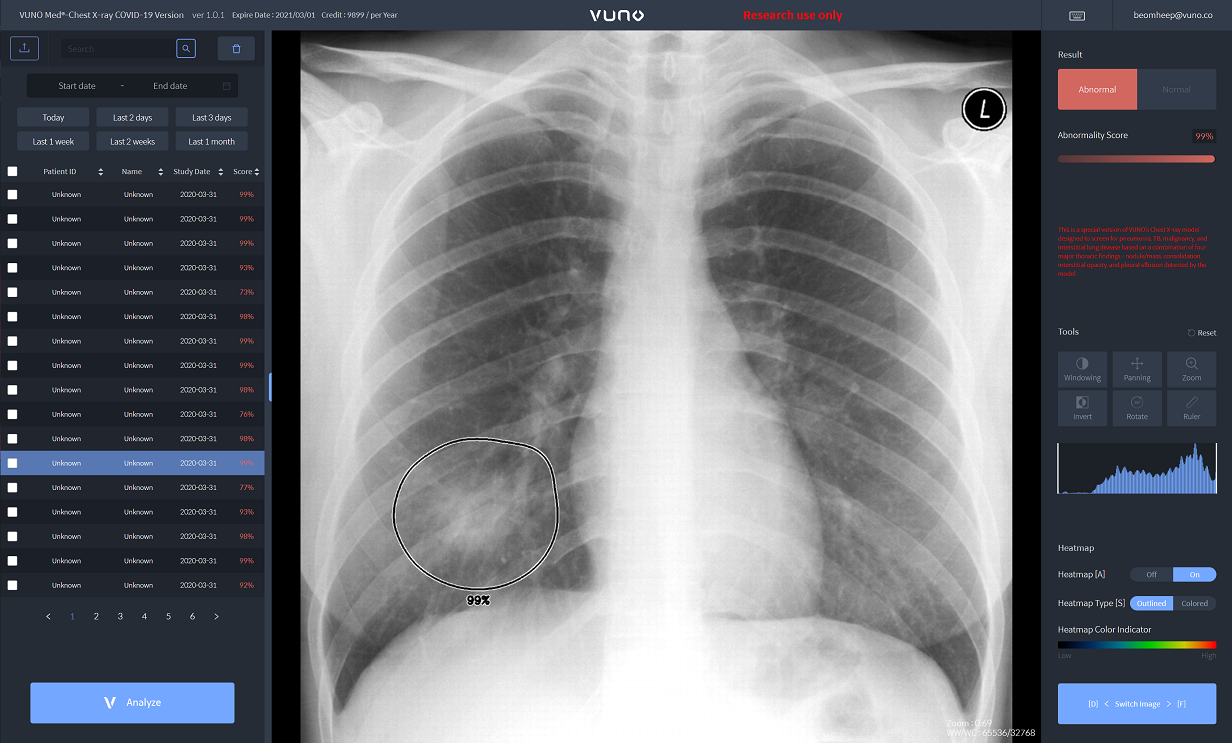

이번에 공개되는 ▲뷰노메드 렁퀀트(VUNO Med-LungQuant) ▲뷰노메드 체스트 엑스레이-코로나19 버전(VUNO Med-Chest X-ray: COVID-19 Version)은 클라우드 기반 웹 서비스다. 전 세계 어디에서나 실시간으로 활용할 수 있다.

뷰노메드 체스트 엑스레이-코로나19 버전은 수초 만에 흉부 엑스레이 영상을 분석, 코로나19로 인한 폐렴 진단에 도움이 되도록 의심 병변과 비정상 여부 소견을 제공한다. 특히 코로나19 폐렴 진단에 도움을 주는 주요 소견인 ▲경화(Consolidation) ▲간질성음영(Interstitial opacity) ▲흉막삼출(Pleural effusion) ▲결절(Nodule)을 실제 환자 데이터를 기반으로 검출할 수 있다.

현재 뷰노메드 체스트 엑스레이는 강원도 지역 보건소에서 환자들의 영상의학적 폐렴 여부를 신속하게 확인하는 등, 코로나19 선별 과정에서 활용되고 있다. 이와 함께 대구파티마병원에서도 지난 1월 해당 솔루션을 도입한 바 있다.